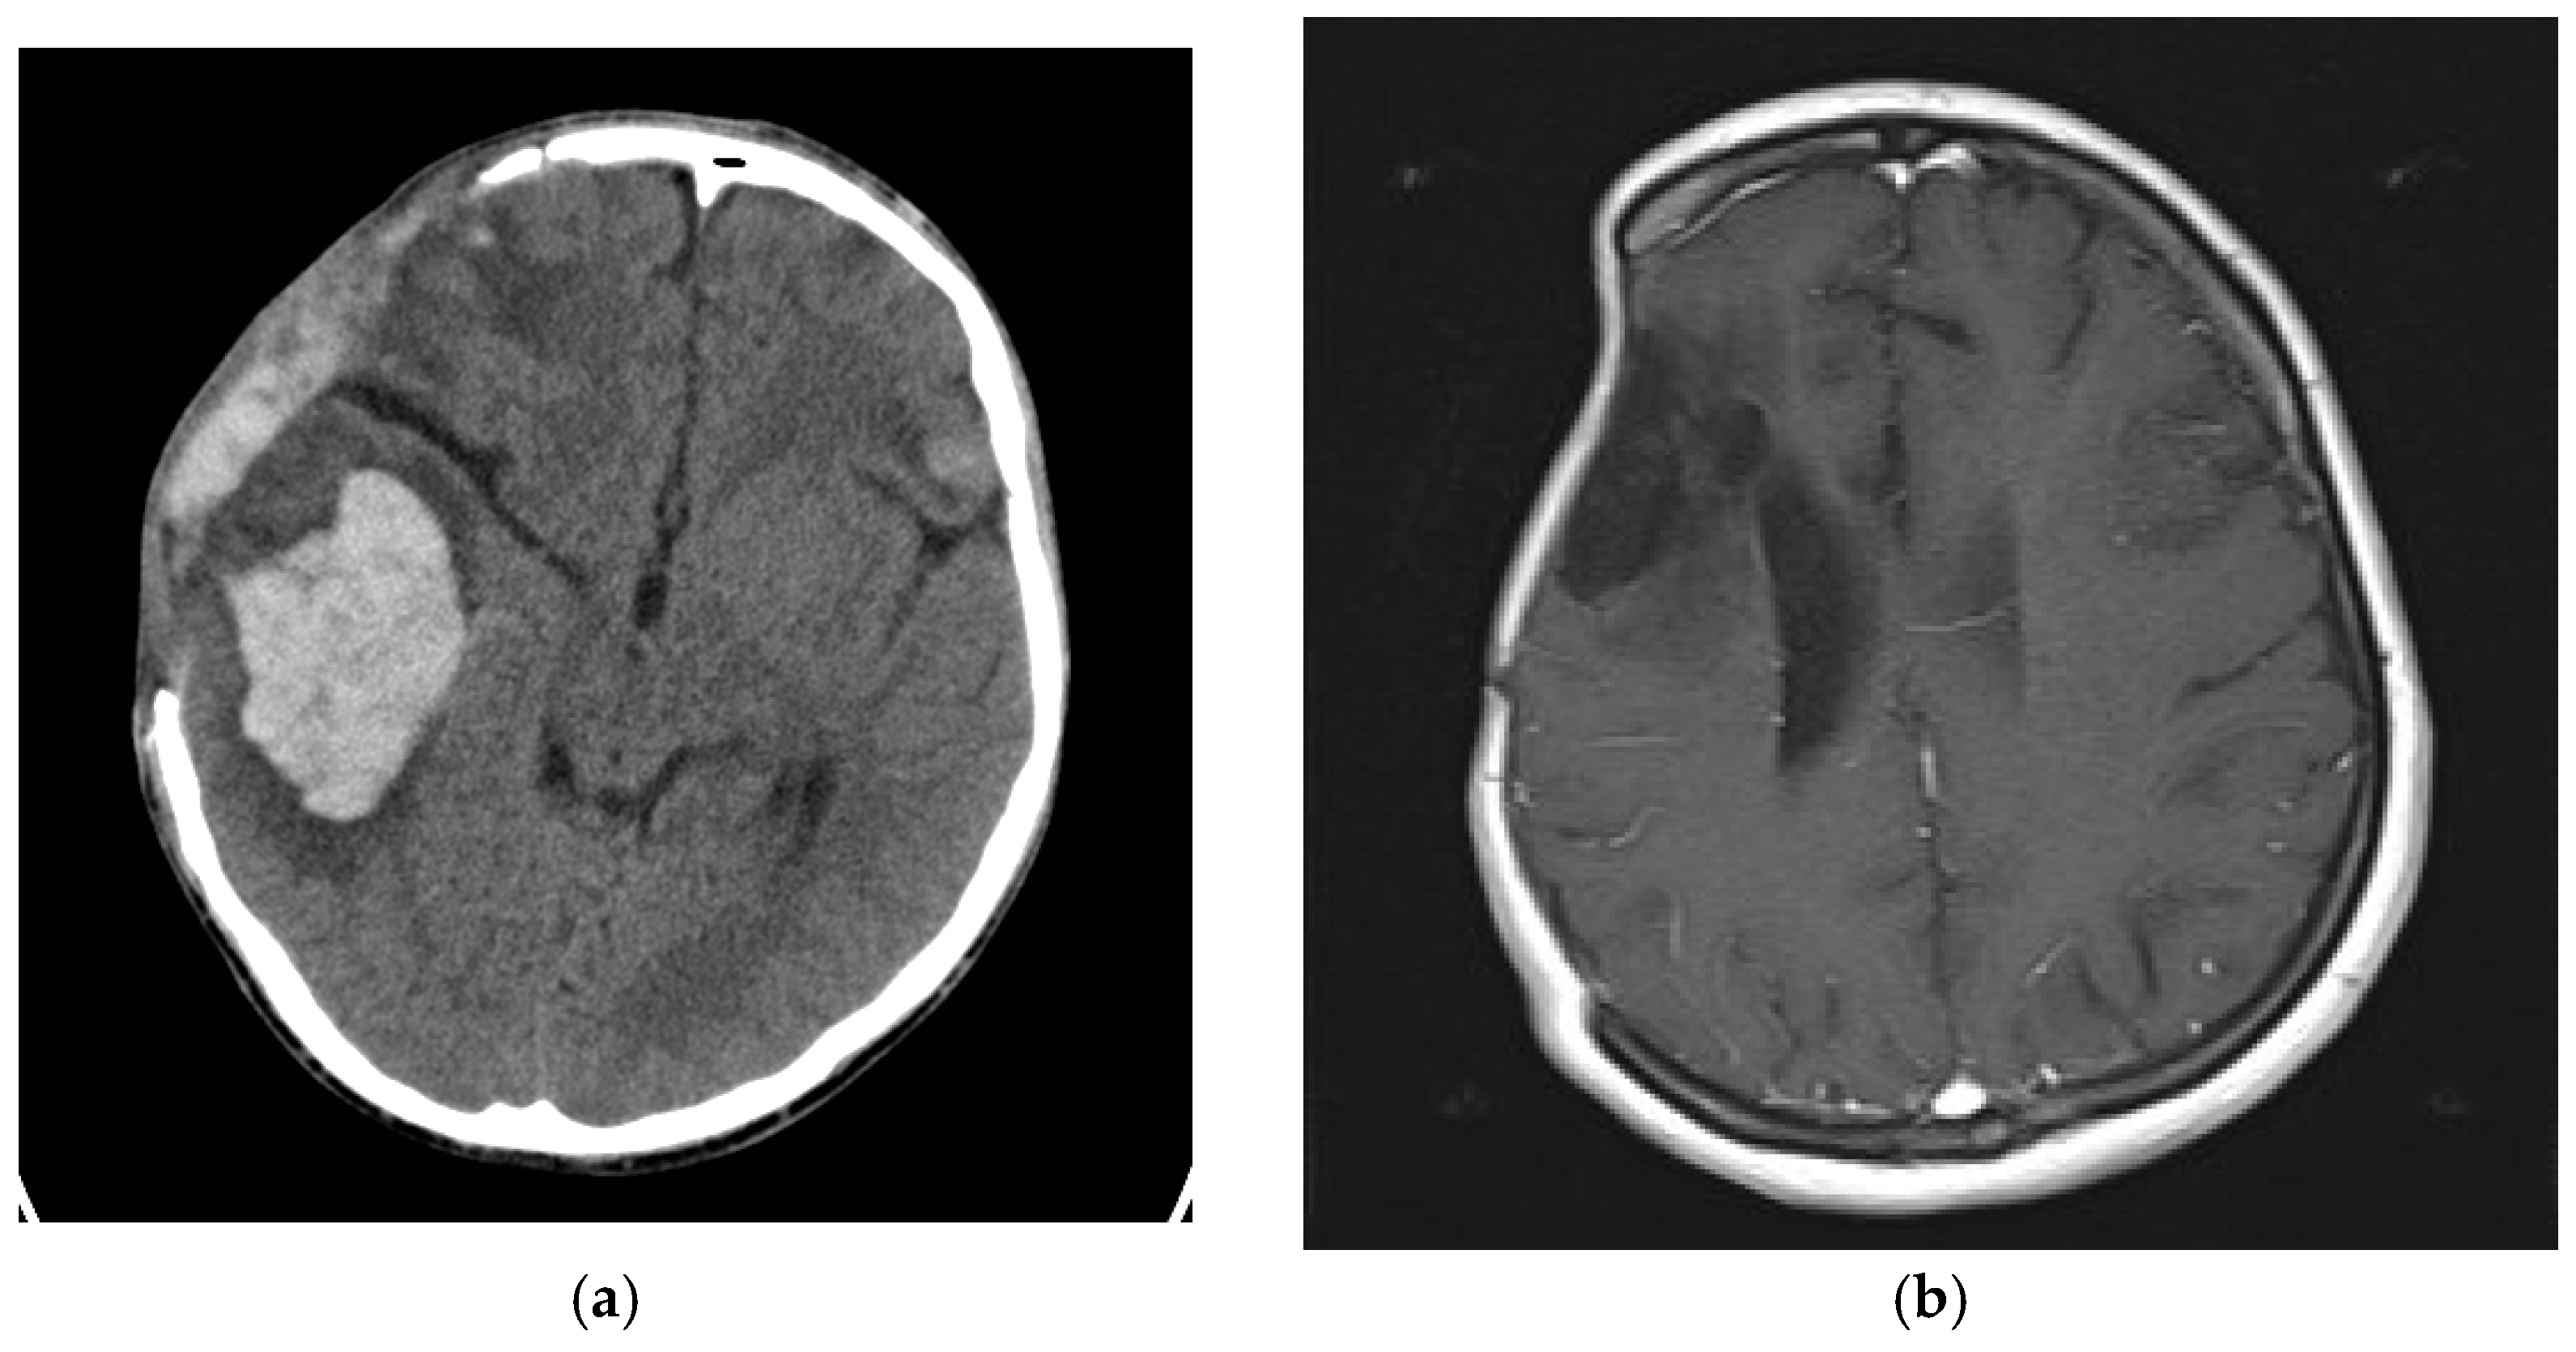

3.2. Radioogical Findings